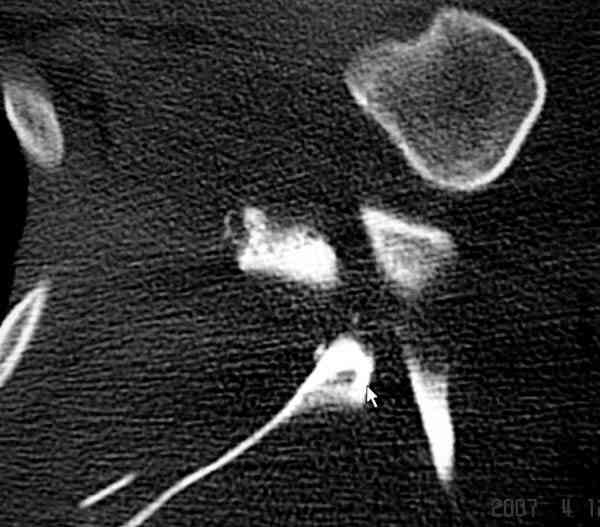

На снимке (№6 компьютерная томограмма и 3D №7) перелом клювовидного отростка.

Передним дельтопекторальным Bankart доступом намного легче провести фиксация отростка, но тогда репозиция и фиксация колонн затрудняется, поэтому был применен стандартный Judet задний доступ.

Репозицию смогли сделать пальцами через щель между

шейкой и телом лопатки (последний 3D снимок)

Двумя шурупами сзади на пластине (вместе шайбы)

провели удержание репозиции, а фиксацию провели

следующим косым шурупом.

Последующие этапы на снимках.